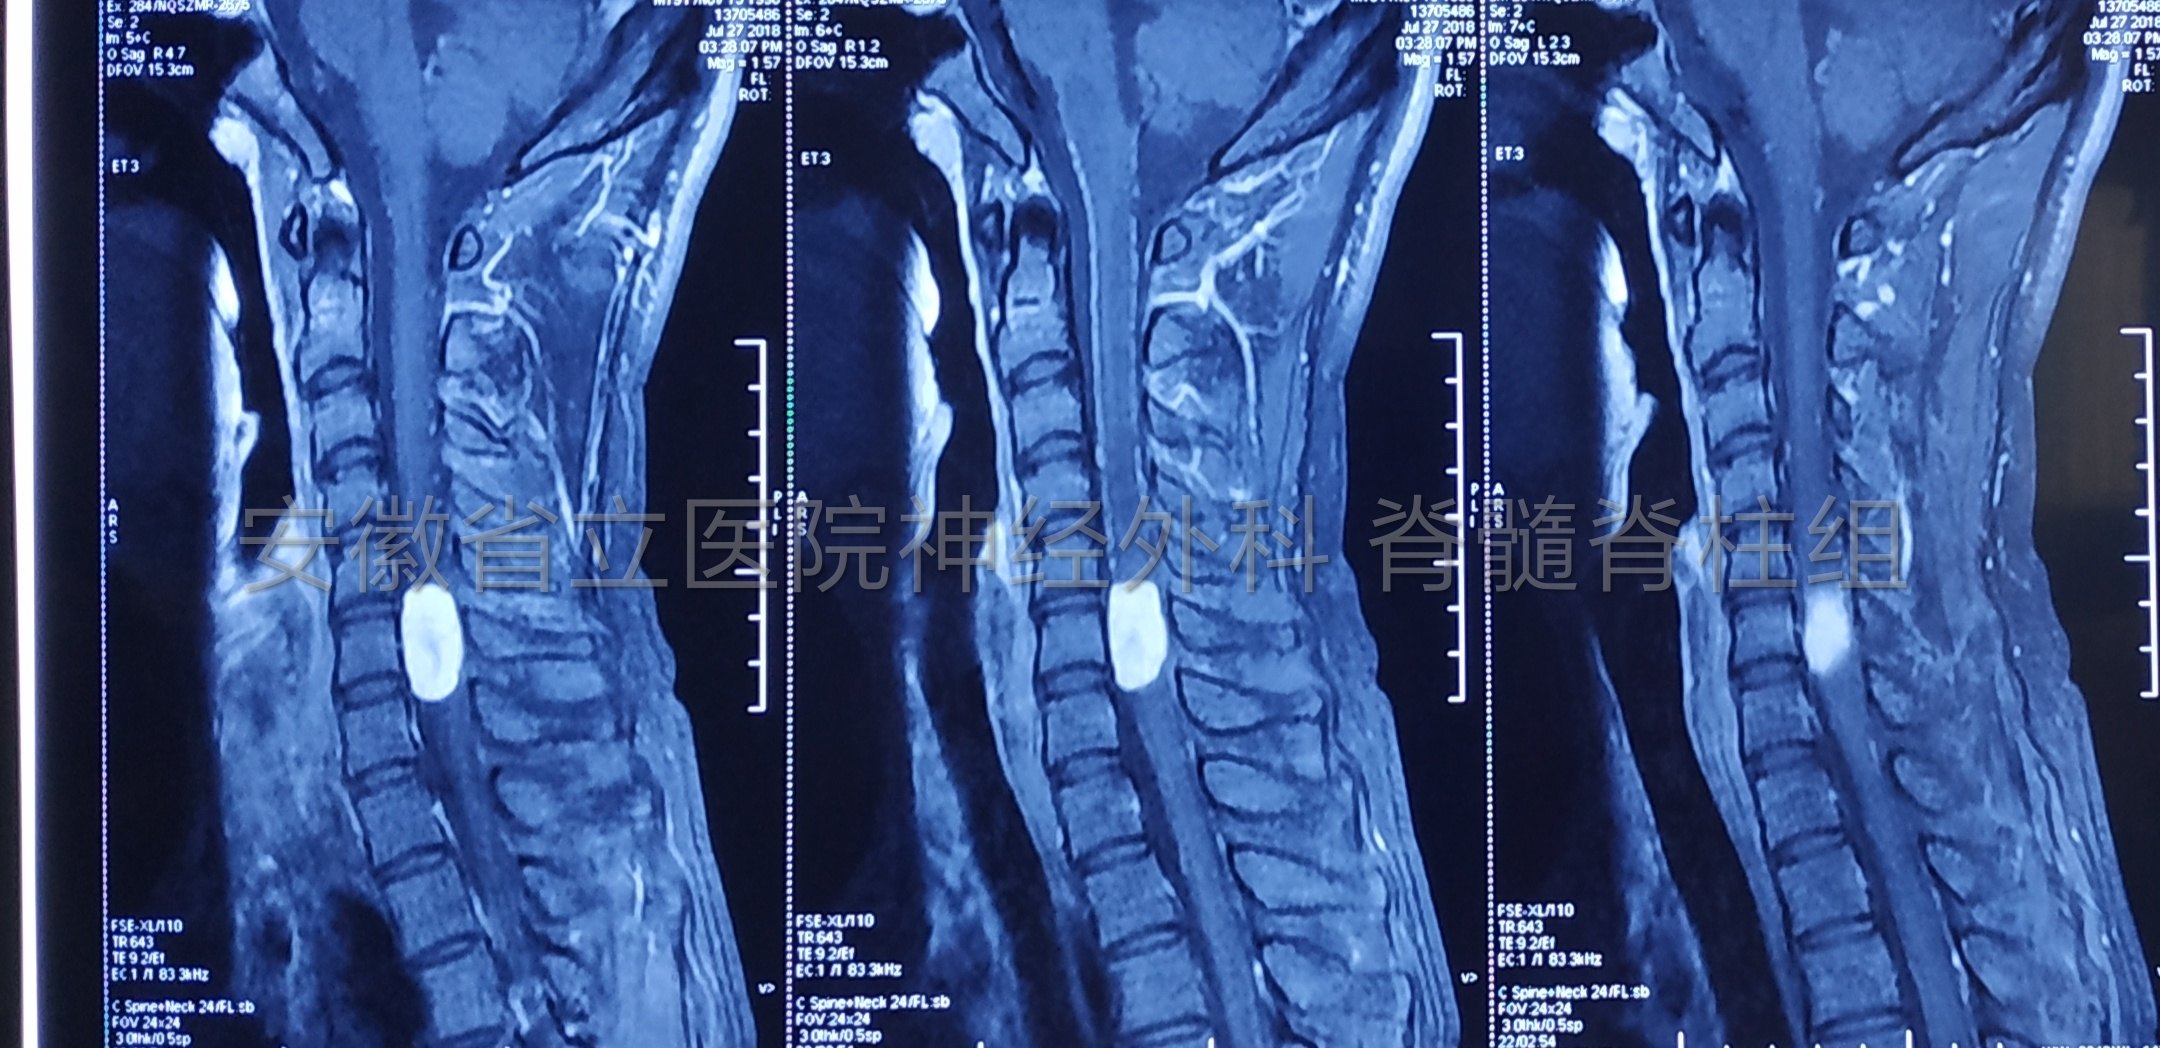

患者17岁,右侧肢体乏力1年入院,查体右侧上肢肌力4级弱,肌肉萎缩。磁共振显示颈椎管占位,完善检查后行手术切除。

手术中全程电生理监测,保护脊髓神经功能完整。

肿瘤切除后予以椎板骨质复位,术后复查显示椎管内肿瘤全切除,骨质复位良好,手术部位解剖完整,患者恢复快,脊柱稳定性得以保证。